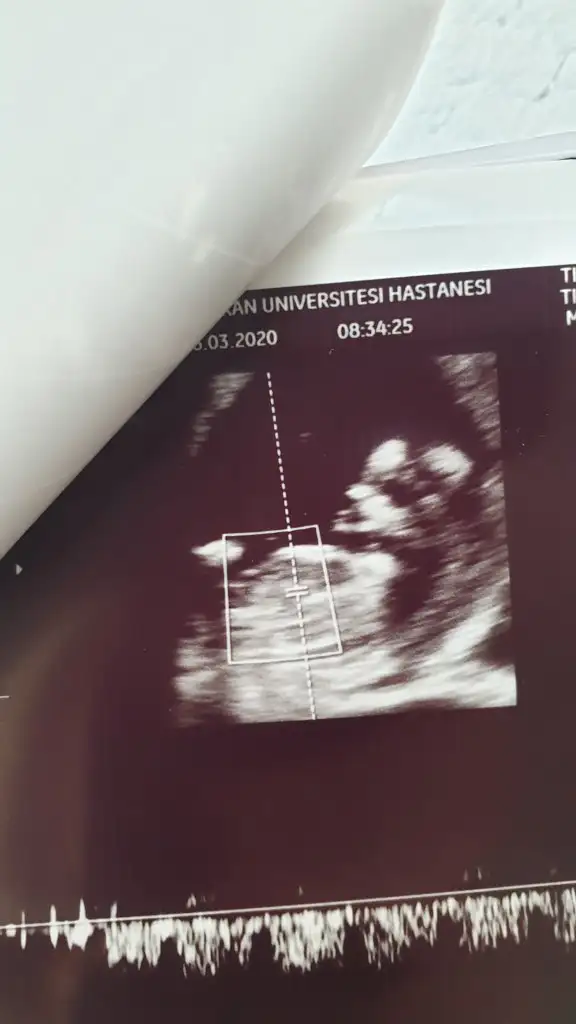

- 5 Mart 2020

- 21

- 10

- 3

tmm ben ayrıntılı ultrasonda netleşince size dönüş yapacağımBencede kız 2 defa kız demiş aynı drusg de nub da kız gibi geri dönüş yaparsanız sevinirim